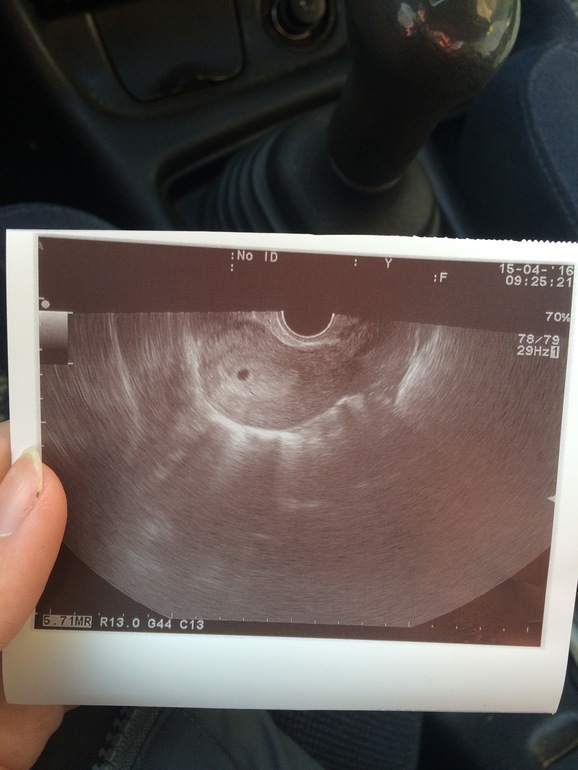

ФолликулометрияПод кат

О это незабываемое чувство))) У меня в 4-5 недель 8 мм было))) ПОЗДРАВЛЯЮ!!!!!

Это точно)))) У тебя такой снимочек четкий.. Там прям будто еще что-то видно (может это ЖТ?) А у меня не такой.. У нас уже 3снимка) И 4 УЗИ)) В 4-5 недель, в 7-8 недель, 9-10 недель (без снимка, в больнице лежали) и в 12 недель скрининг)) Теперь ломка, хочу на УЗИ, а кабинета платного здесь нет... Ждем скрининга(((